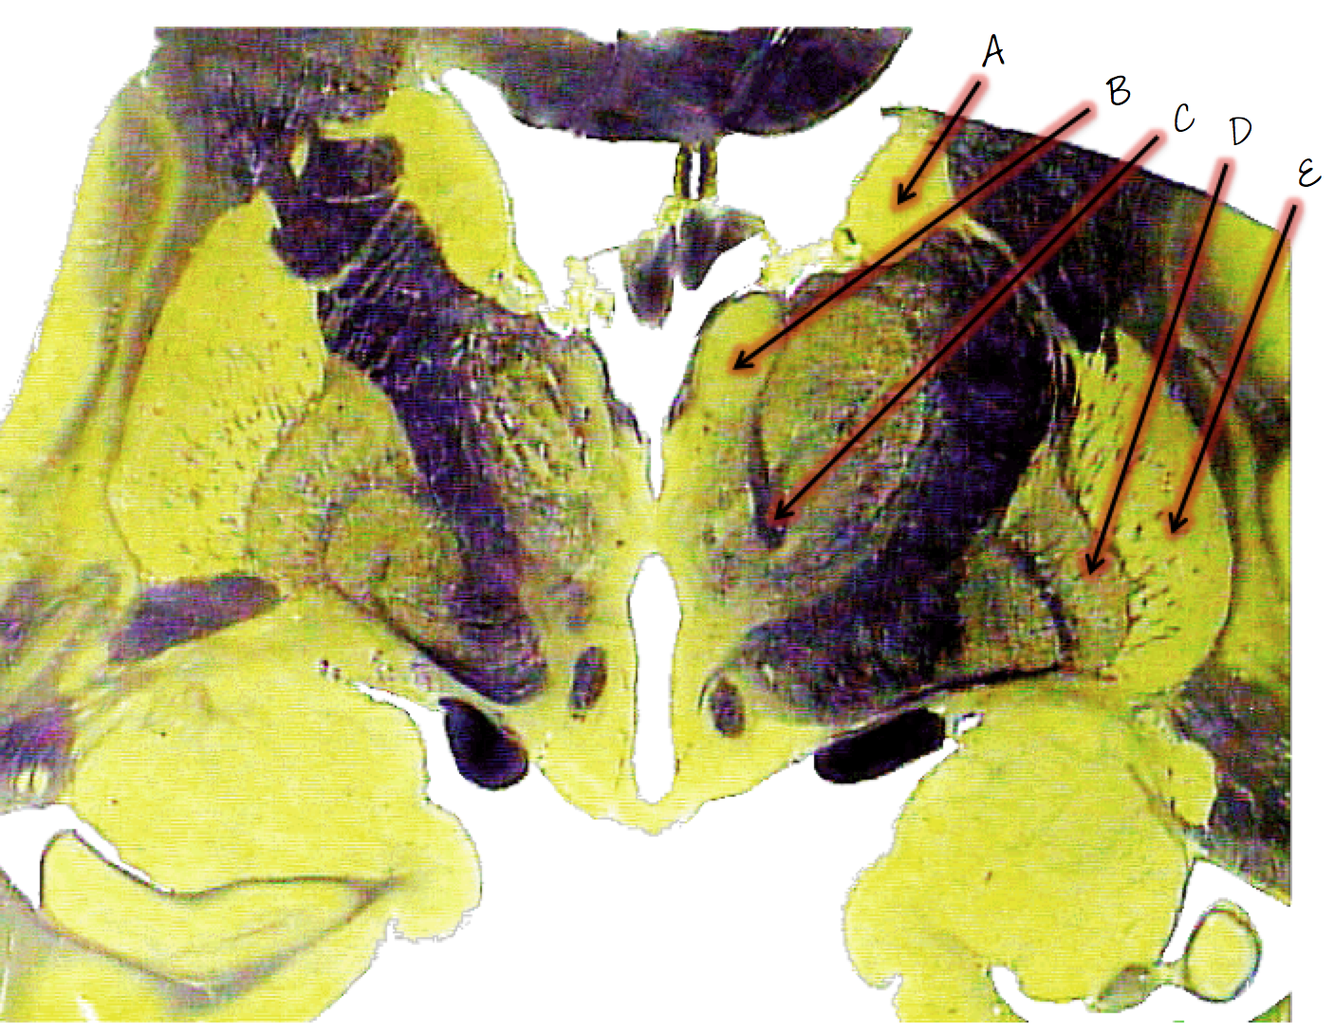

A: caudate nucleus

B; anterior nucleus of thalamus

C; mammillothalamic tract

D; globus pallidus

E; putamen